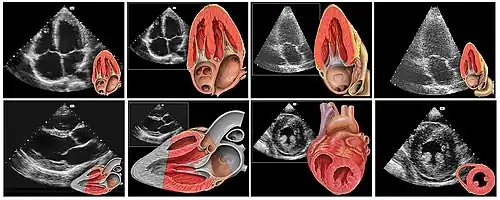

Le cœur est un organe intra thoracique, entouré d'air (les poumons) et d'os (les côtes). Ces deux dernières structures ne laissent pas transmettre les ultrasons, rendant l'examen plus complexe. On se sert ainsi d'un nombre limité de « fenêtres » anatomiques, lieux où le cœur peut être visualisé par l'échocardiographie, sans interposition aérienne ou osseuse.

Le patient est installé torse nu, allongé sur le côté gauche (décubitus latéral gauche). Il n'a pas besoin d'être à jeun. Éventuellement, trois électrodes sont collées afin de disposer d'un tracé ECG simultané. L'examinateur, suivant son habitude, est à la droite ou la gauche du patient. Il applique la sonde d'échographie recouverte d'un gel (permettant un meilleur passage des ultrasons à travers la peau) sur la peau de ce dernier suivant différentes positions constituant les fenètres d'échographie dont les principales sont :

- « Voie para sternale gauche » : entre la troisième et la quatrième (voire entre la quatrième et la cinquième) côte, juste à gauche du sternum ;

- « Voie apicale », partie inférieure gauche du sternum, là où est perçu le mieux à la palpation le battement cardiaque (« choc de pointe ») ;

- « Voie sous costale ou sous xyphoïdienne », dans le creux en dessous de la xiphoïde du sternum.